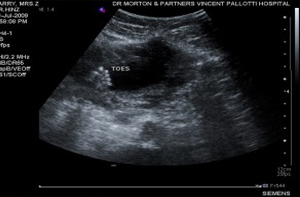

minus 6 months – Mum’s not well Zuhre wasn’t well. She had stomach pains, swollen abdomen and was feeling nauseous in the morning. Pregnancy was out of the question according to our [...] January 6, 2010